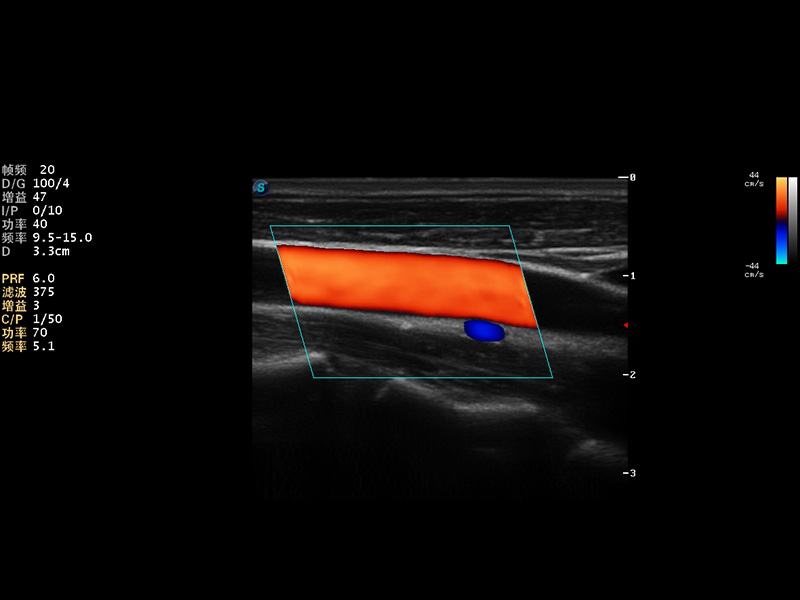

S9便携式彩色多普勒超声诊断仪是乐玩lewin国际研发的高端便携彩超设备,外观设计新颖、产品性能卓越。S9在便携超声领域采用了突破传统的触摸屏交互设计,并以先进的软件硬件技术和设计理念,为您带来清晰的图像质量、稳定的工作性能和便捷的操作体验。

AutoC智能血流追踪